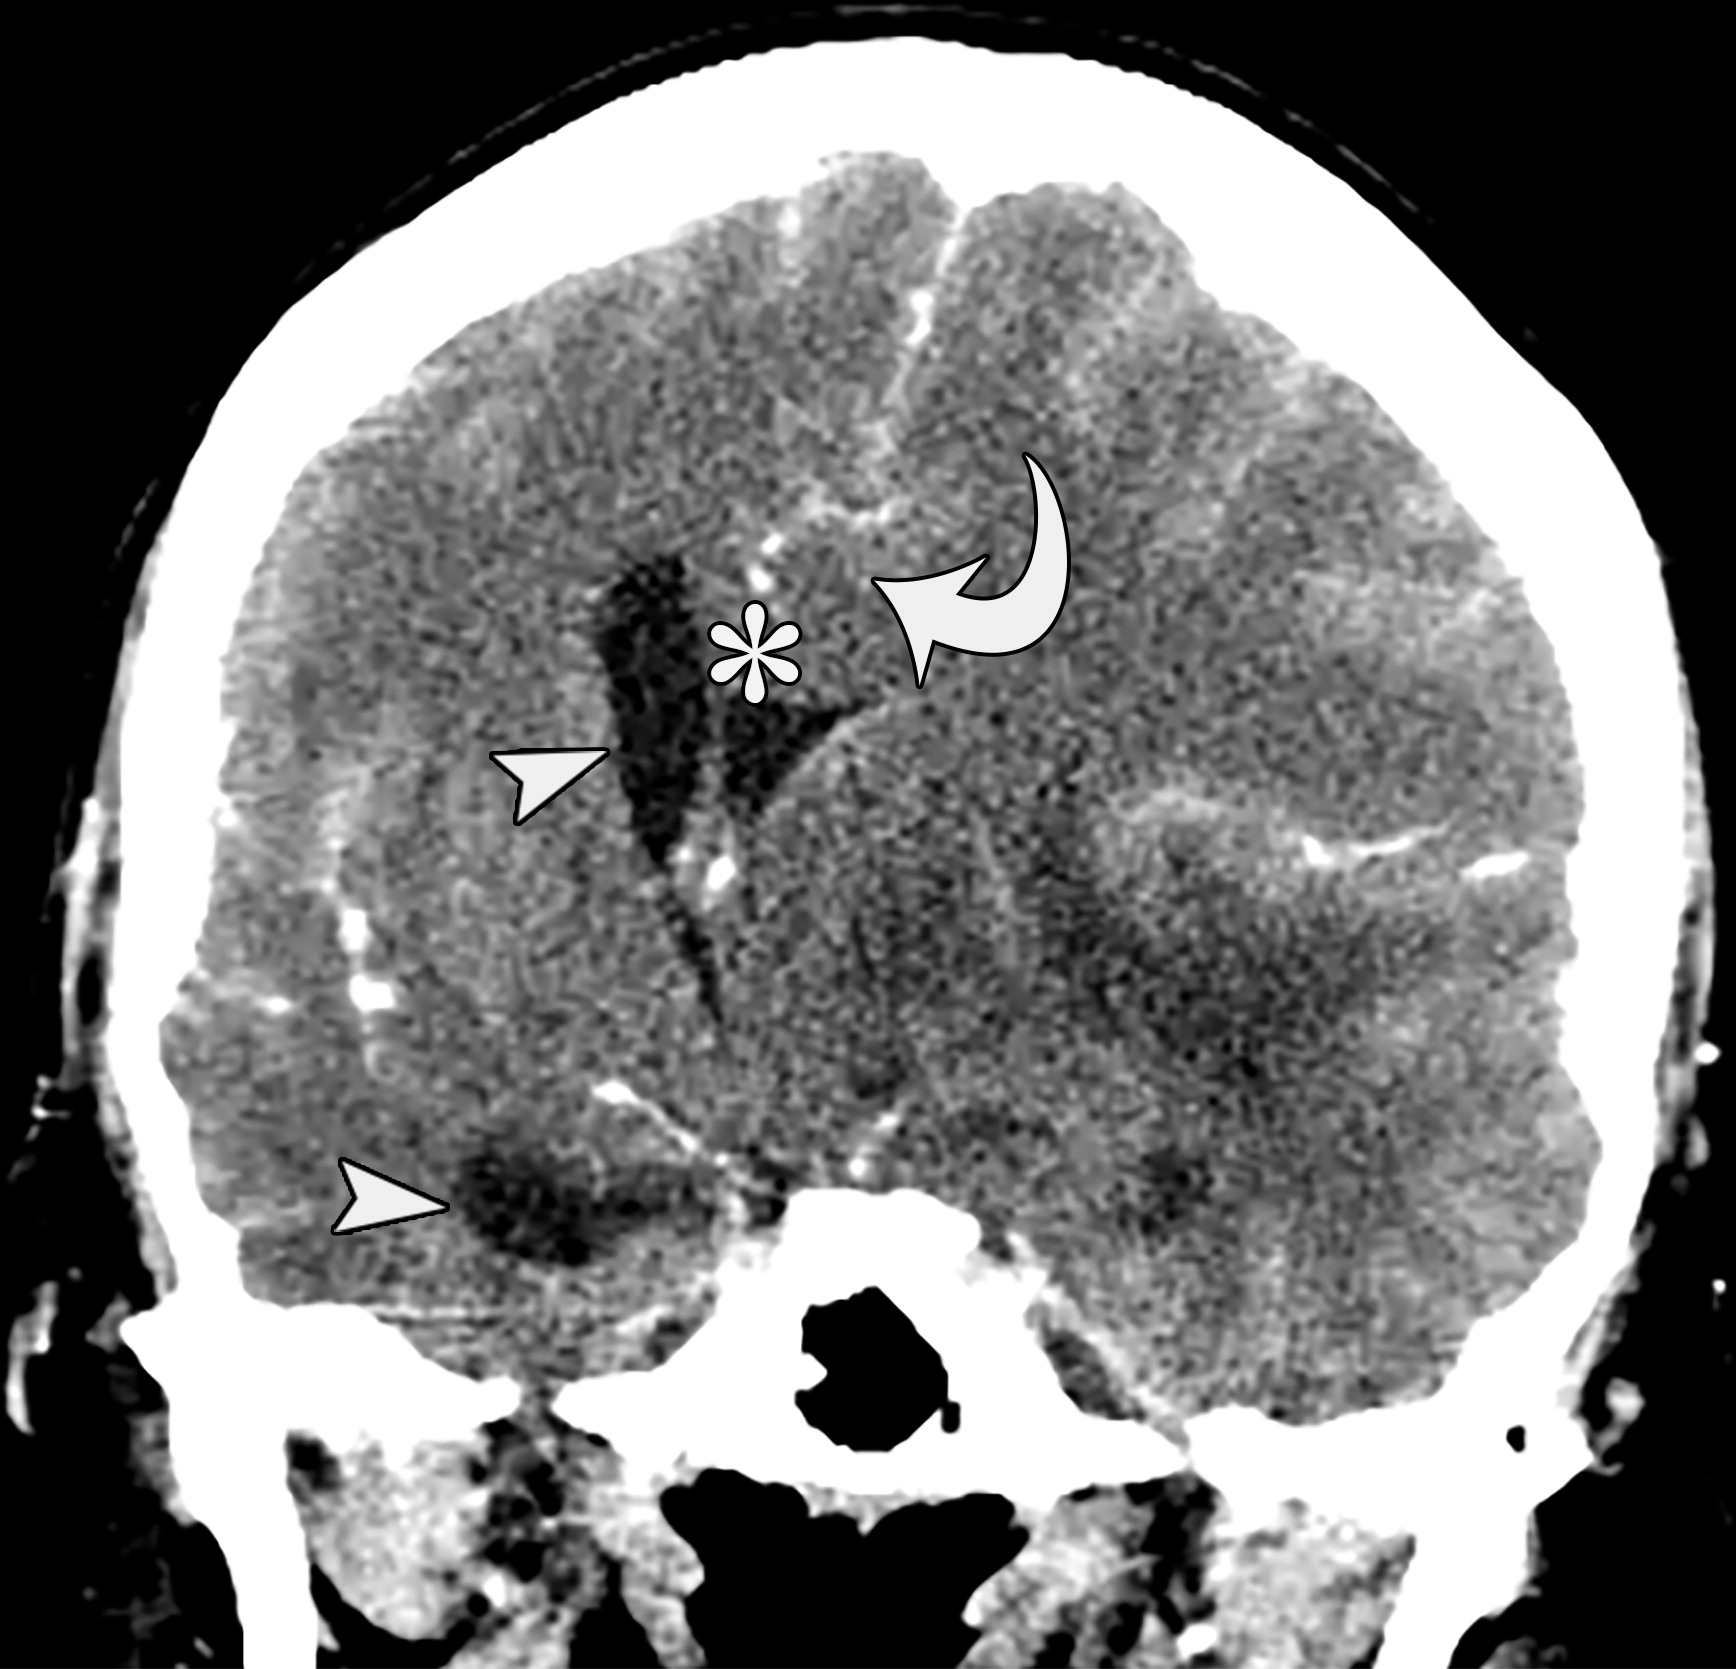

大脑镰下疝。平扫轴位CT示:右侧硬膜下血肿(*)伴混合密度影,表明处于不同时期的血液,血肿推挤使透明隔相对于中线(白色虚线)向左侧移位(白色长箭头)。右侧侧脑室受压,但是左侧侧脑室扩张。

e10b81f69aecfde7ed5f5612478dbcdc.jpeg

33岁男性,生殖细胞肿瘤脑转移患者的大脑镰下疝:冠状增强CT示大脑穹隆游离缘下方的扣带回从左向右疝入(白色弯箭头),并伴同侧胼胝体(*)的下侧移位,注意同侧脑室受压和对侧脑室的扩张(白色箭头)。